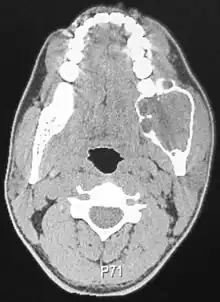

Radiographically, the tumour area appears as a rounded and well-defined lucency in the bone with varying size and features. Numerous cyst-like radiolucent areas can be seen in larger tumours (multi-locular) giving a characteristic "soap bubble" appearance. A single radiolucent area can be seen in smaller tumours (unilocular).[8] The radiodensity of an ameloblastoma is about 30 Hounsfield units, which is about the same as keratocystic odontogenic tumours. However, ameloblastomas show more bone expansion and seldom show high density areas.[14]

Lingual plate expansion is helpful in diagnosing ameloblastoma as cysts rarely do this. Resorption of roots of involved teeth can be seen in some cases, but is not unique to ameloblastoma.[10]